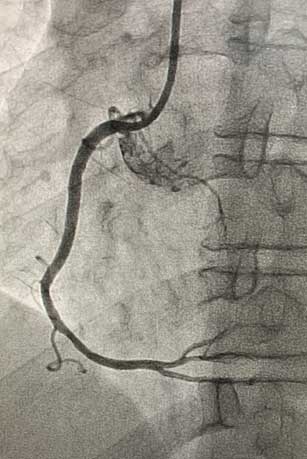

患者为45岁男性,因间断发作剑突下疼痛10天就诊于我院心血管内科门诊,完善检查后以“冠心病、不稳定型心绞痛”收入心血管内科病房。冠脉造影示:右冠近中段90%节段性狭窄,与冠脉CTA诊断一致。患者右冠状动脉近中段存在重度狭窄病变,有植入冠脉支架指征。心血管内科介入团队在赵慧强主任的带领下,针对此患者制定了个体化介入治疗方案:患者的病变特点为右冠状动脉近中段病变,无严重钙化、迂曲,非左主干病变、分叉病变、小血管病变,且患者年龄较轻,综合考虑远期预后效果,此患者适用于植入生物可吸收支架。冠脉介入团队进行了详细的术前讨论和充分的准备,经过患者同意后,为其行生物可吸收支架植入术。术中,经过充分预扩张处理右冠状动脉近中段狭窄病变后,成功于右冠状动脉病变处植入一枚生物可吸收支架。术后即刻复查冠脉造影:右冠状动脉中段支架膨胀贴壁良好,手术成功。

生物可吸收支架植入术后.jpg术后